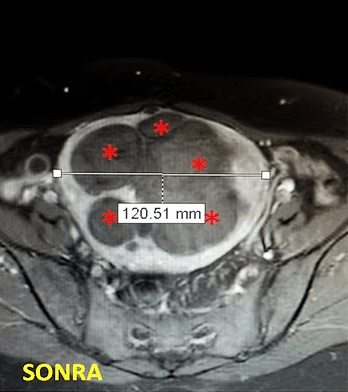

32 yaşında, kansızlık, gaz, sık idrara çıkma şikayetleri var. Emar’da 9 cm çaplı tek miyom (*) mevcut. Tek seans perkütan ablasyon sonrası miyomun belirgin küçüldüğü izleniyor. İşlemden 5 ay sonra hasta şikayetleri kalmamıştır.